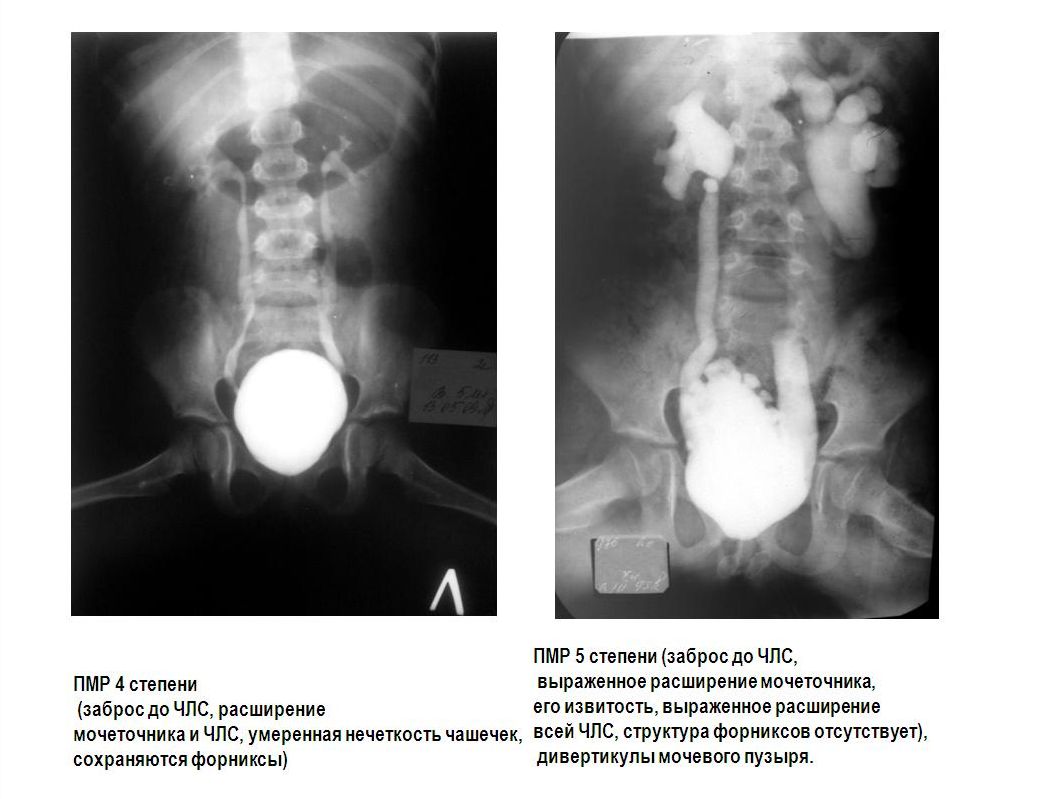

Рефлюксирующий мегауретер: Визуализация и медицинские изображения